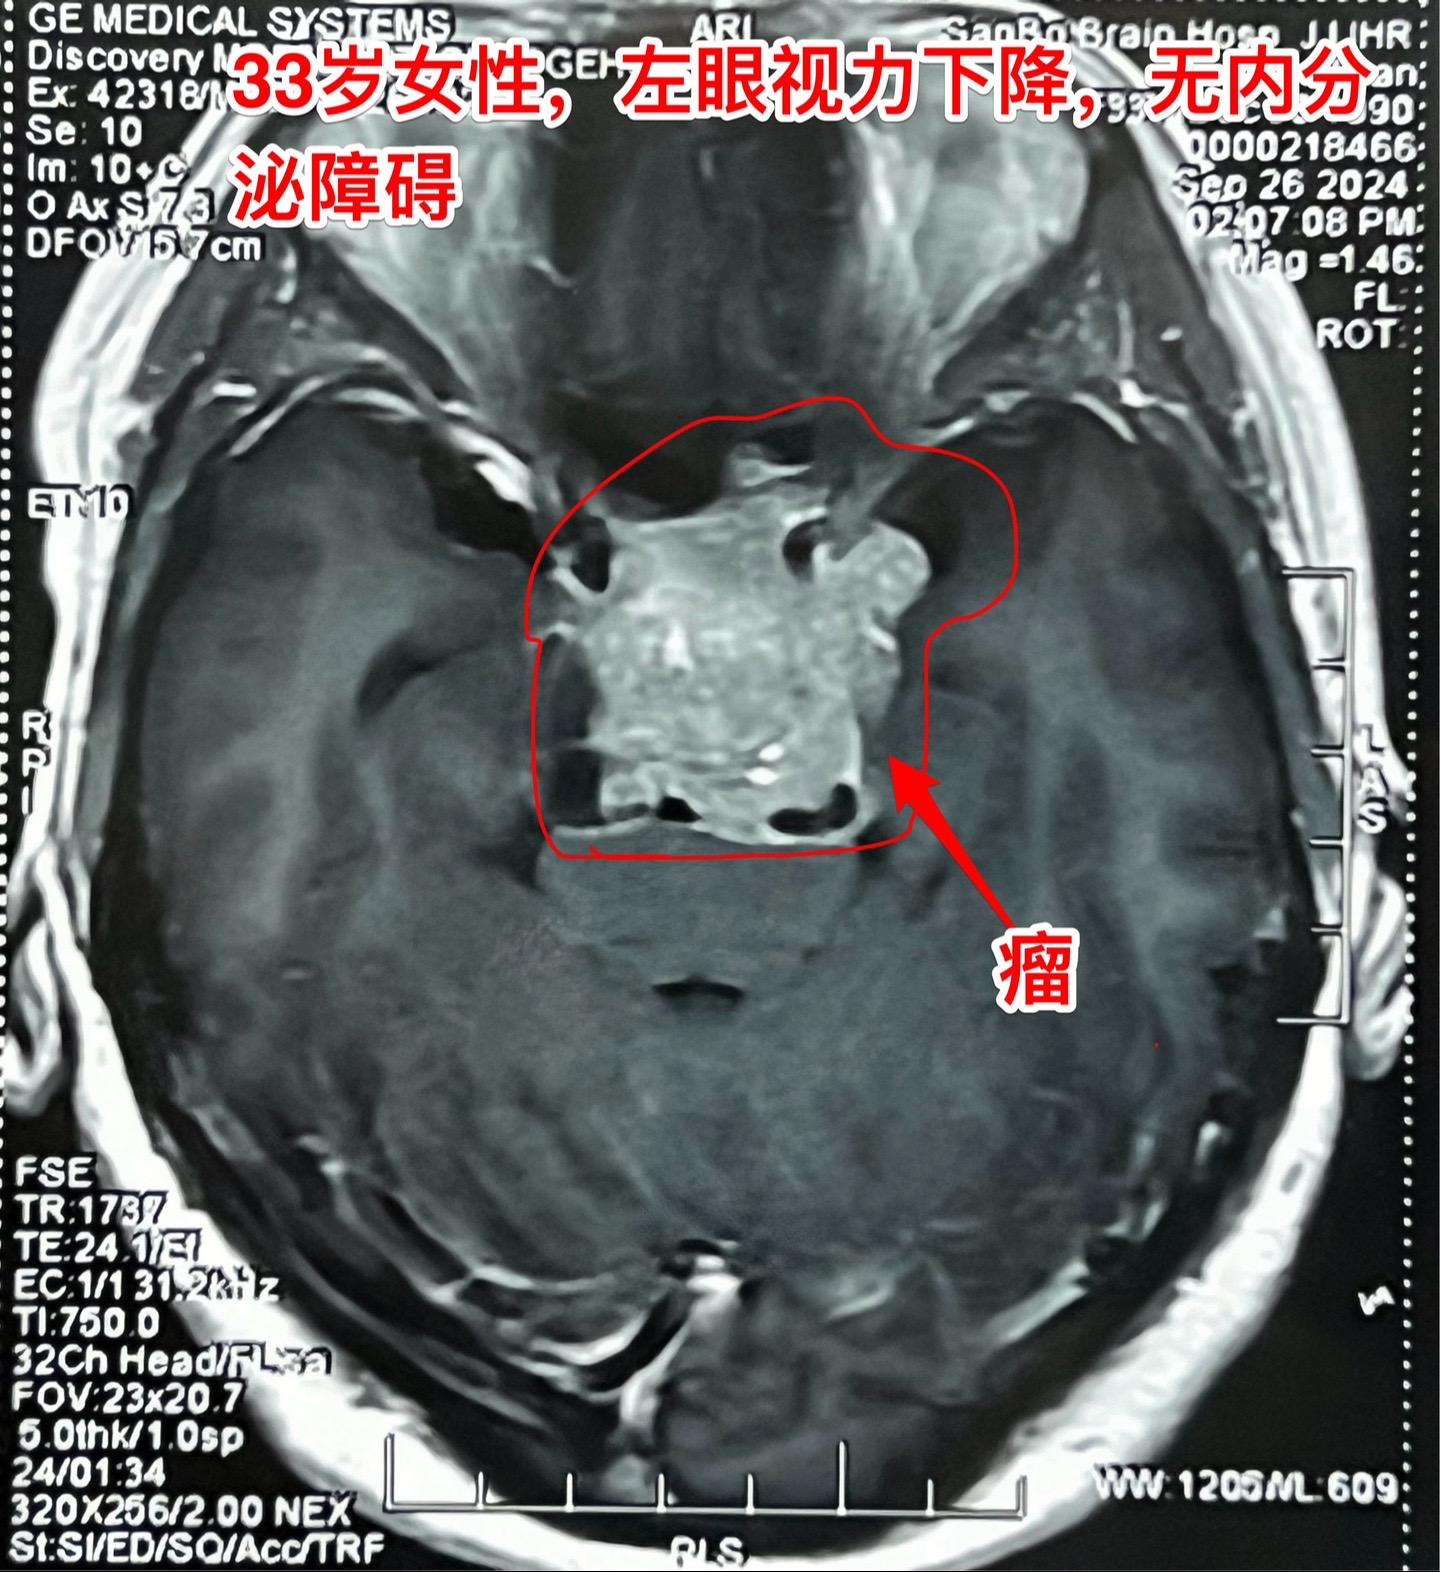

国庆节长假后第一天完成两个手术。一个手是33岁女性,来自云南省香格里拉。因左眼视力下降,到医院检查发现鞍区肿瘤,怀疑是颅咽管瘤。病人没有内分泌功能障碍。影像学上肿瘤是实性的,没有钙化,而且可以看见垂体信号。到底是什么肿瘤呢?今天手术中取肿瘤标本作快速冰冻病理检查,报告是垂体瘤。肿瘤得到完全切除,手术后病人视力好转了。 另一个手术是11岁男孩子,颅咽管瘤复发。经原切口翼点入路将肿瘤完全切除。术前磁共振只看见一个圆形肿瘤,术中发现除了这个肿瘤外还有5个散在的钙化斑,均得到完全切除。这样的散在钙化斑是潜在的危险因